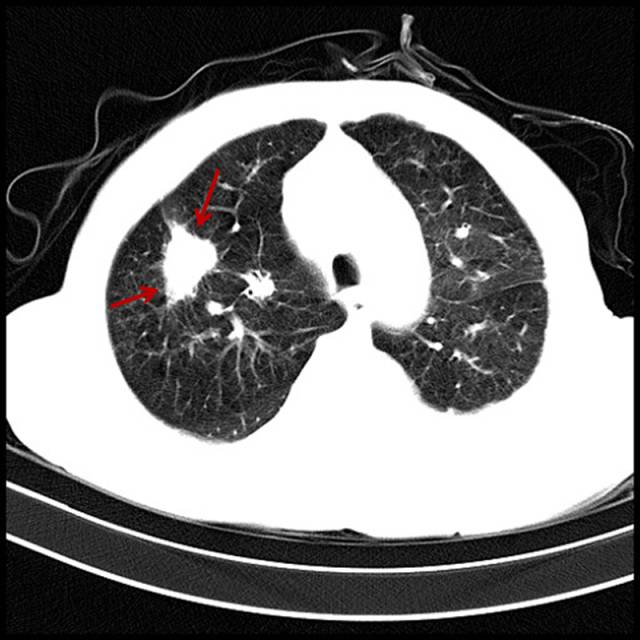

■吸烟导致肺癌

男,79岁,吸烟。